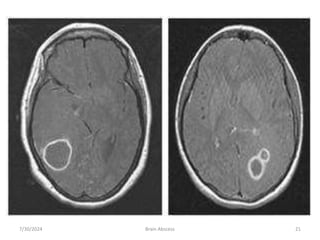

• MRI :

• T1 :

• necrotic center ( hypointense)

• Capsule ( hyperintence)

• Edema ( hypointence)

• T2 :

• necrotic center ( hyperintence)

• Capsule ( hypointence)

• Edema ( hyperintence

7/30/2024 Brain Abscess 18